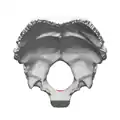

Le foramen magnum (ou trou occipital) est un orifice de forme ovale de l'os occipital[1].

Le foramen magnum est situé à la base du crâne entre l'écaille de l'os occipital , sa partie basilaire et ses deux parties latérales.

Latéralement, il est délimité par les condyles occipitaux.

Son diamètre antéro-postérieur est en moyenne de 35 mm et son diamètre transversal de 30 mm.

La région médiane du bord antérieur du foramen magnum constitue le basion et a partie médiane de son bord postérieur constitue l’opisthion, qui sont deux points de repère crâniométriques.